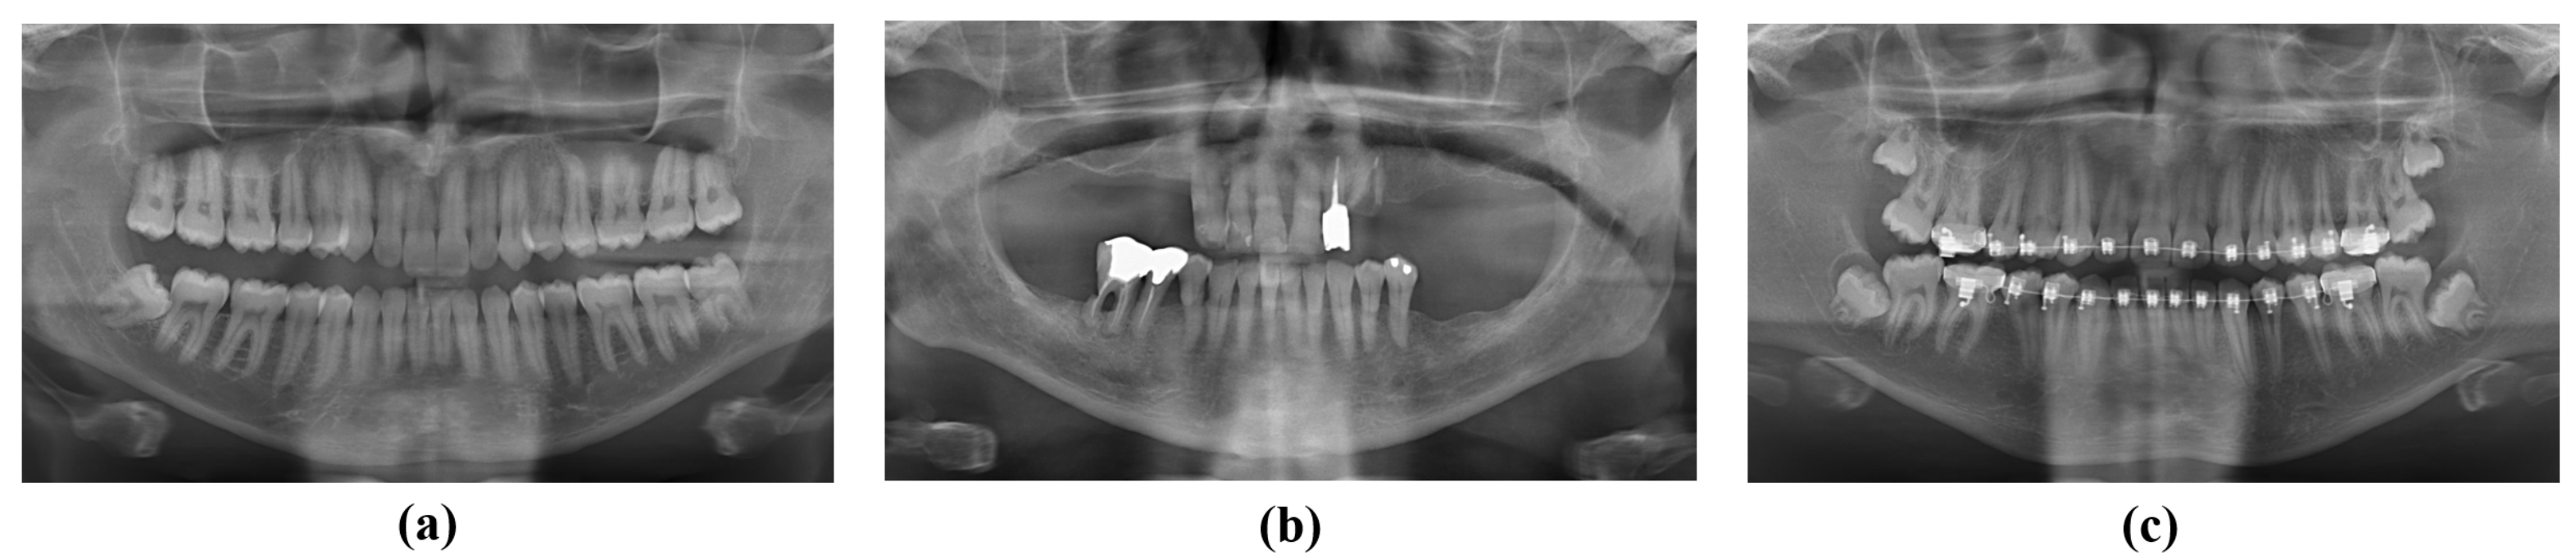

2.1.1. Tooth Instance Segmentation Dataset

2.1.2. Missing Tooth Regions Detection Dataset